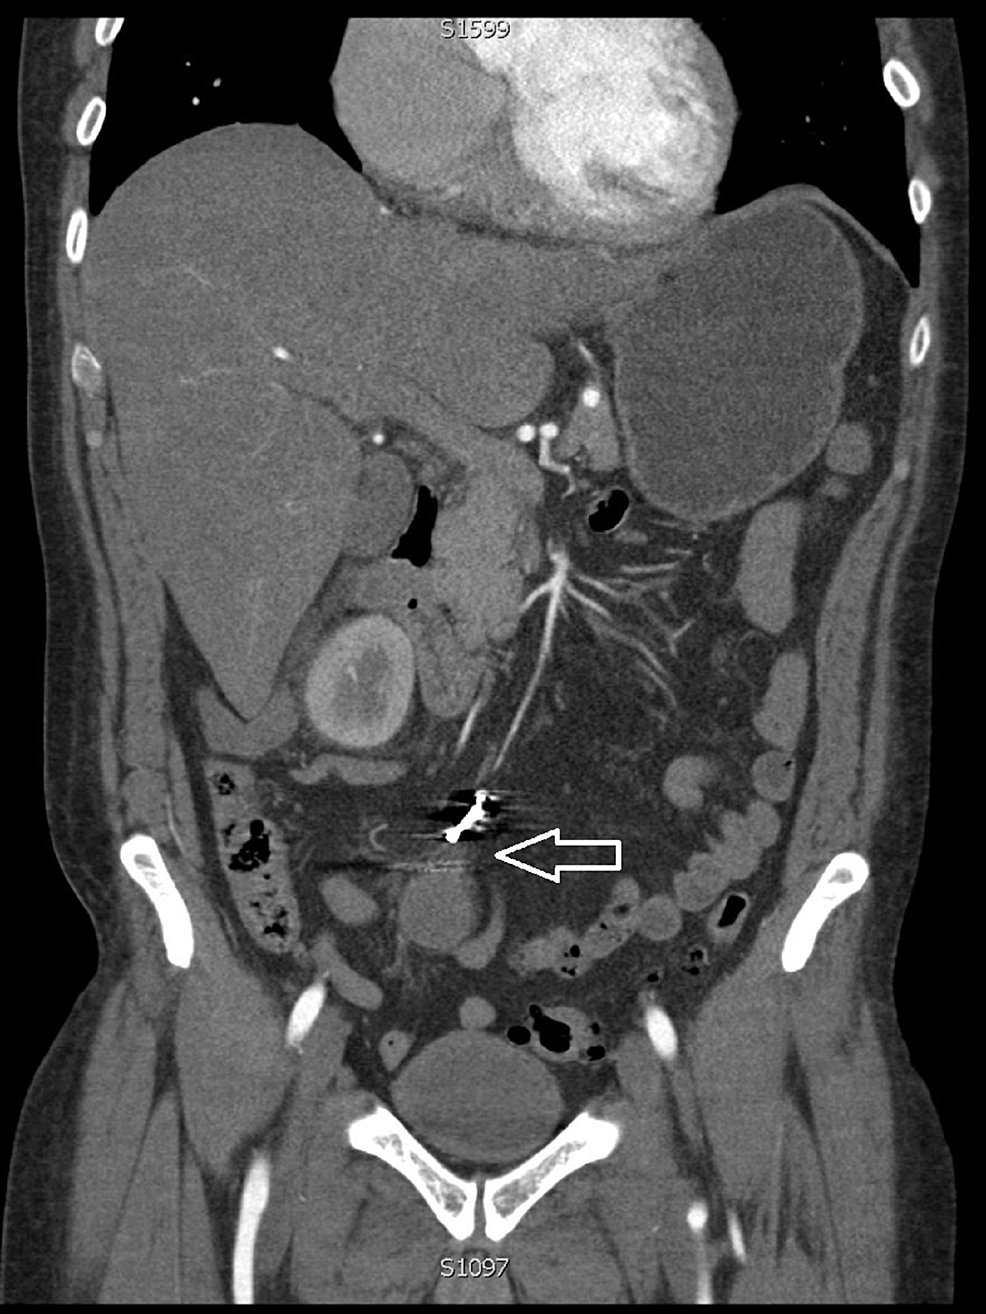

(A and B) Contrast tomography of the abdomen in coronal and axial views

(A and B) Contrast tomography of the abdomen in coronal and axial views Coils In Stomach Side effects of an ius (intrauterine system), also called a hormonal coil, are most common for a few months after having it fitted. Find out about an iud (intrauterine device) or copper coil, including who can use it, how well it works and possible side effects. It is very safe and has few side effects, but it can make. It. Coils In Stomach.